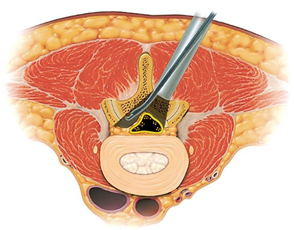

上図のように、FESS法には2つの経路があります。側方経路が椎間孔アプローチ、後方経路が経椎弓アプローチといわれています。手術術式はそれぞれのケースで異なっています。

経椎弓アプローチで椎間板ヘルニアを摘出(左)、MELと同様に片側進入両側除圧が可能で、PEL法ともいわれています。PEL法は術後硬膜外血腫のリスクが高いので、血液を創から排出するためのドレーンを長く(4日程度)留置します。